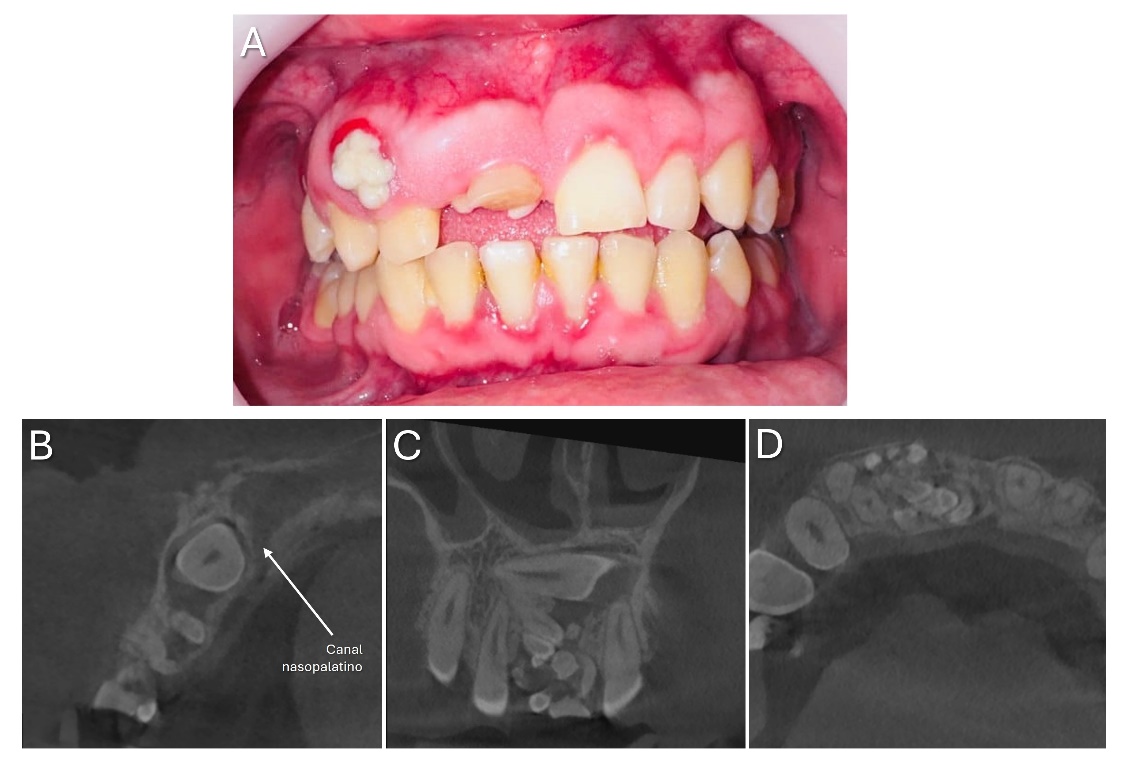

Hombre de 25 años acude al Servicio de Radiología de la Facultad de Odontología de la Universidad Nacional Autónoma de Honduras para extracción de lo que él consideraba como dientes supernumerarios de 9 años de evolución y con dolor hace 1 semana. Además, el paciente relata incomodidad estética. Clínicamente se observó un aumento de volumen en el sector anterior del maxilar de consistencia pétrea con aspecto lobulado y radiográficamente se confirma la presencia de la lesión (Figura 1).

Figura 1. En la imagen clínica (A) se observa la persistencia del diente deciduo y aumento de volumen de color blanquecino con bordes eritematosos debido al depósito de biofilm e inflamación gingival. En la imagen radiográfica (B) se observa el diente incisivo central superior derecho incluido en posición horizontal con su corona en relación a una lesión mixta rodeada por un halo hipodenso y presencia de varios dentículos.